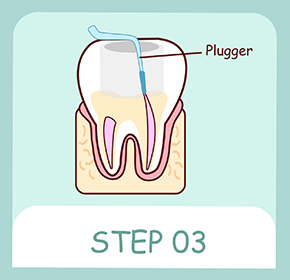

消毒が終わったら、細菌が繁殖しないように充墳剤を入れて密封します。